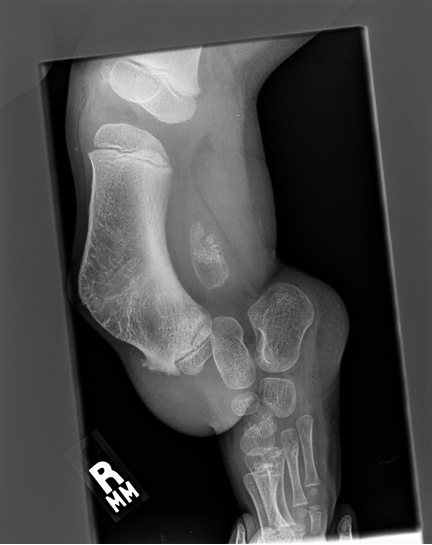

Foot

- small limb / foot

- absent lateral ray(s)

- lateral tarsal bones fused or absent

Ankle

- equino-valgus / ball and socket

- tarsal coalition